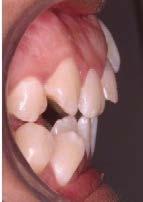

En su análisis facial la paciente presentó un perfil convexo con un tercio inferior aumentado, patrón dolicocefálico severo de VERT, sonrisa gingival e incompetencia labial (Figura 1 A). Durante la exploración intraoral encontramos mordida abierta anterior con apiñamiento severo superior (-13mm) e inferior (-11.5mm), líneas medias desviadas y no coincidentes con la línea media facial, el diente 11

mutilado y con tratamiento de conducto inconcluso, overbite -3mm y overjet 8mm (Figura 1 B).

Extraorales: Frente y perfil. B) Intraorales: oclusales, laterales y sobremordidas.

Figura 1. Fotografías iniciales. A)